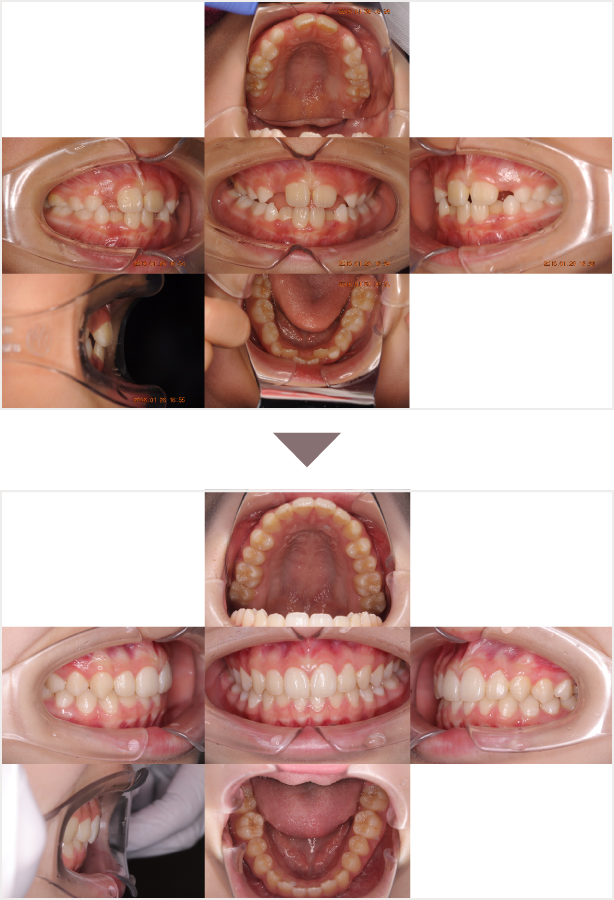

症例叢生

性別

期間6年10ヶ月

治療内容N-Bimler装置、Neo-Capを使用して治療

治療における

副作用・リスク

装着しないと効果は出ません

金額ビムラー装置:550,000円

ネオキャップ:8本

合計:594,000円